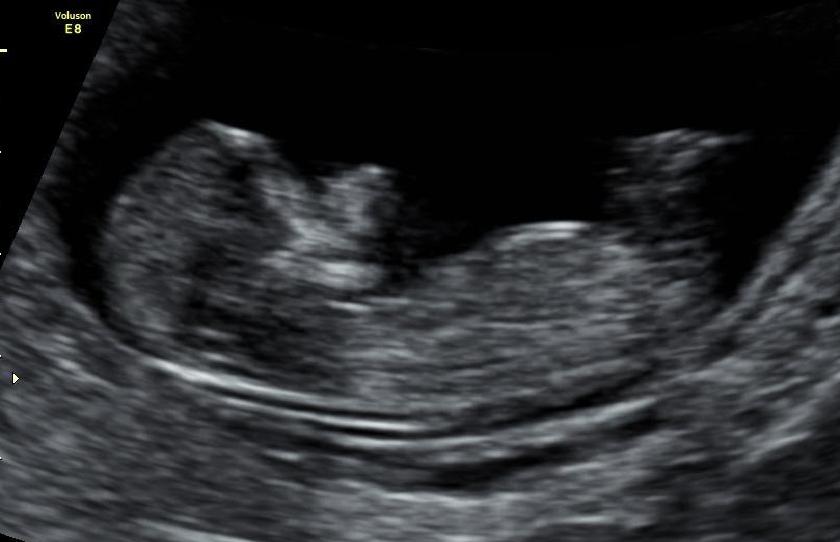

Hi nub geniuses. This photo was taken at 12 wks 3 days. Baby measured 12 wks 6 days. Is that huge line a nub? Please let me know. Thank you!

Yeah, that white line is the nub. And it's pretty girly :)